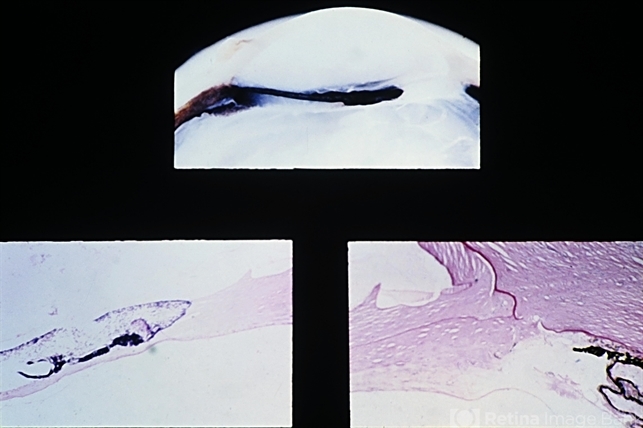

- updrawn pupil, cataract extraction, vitreous, iris leaf, fibrous tissue, cataract

- Updrawn pupil following cataract extraction. Vitreous is incarcerated in the cataract scar above. The inferior iris leaf is adherent to fibrous tissue that has proliferated along the tract of the anterior vitreous. Contraction of this fibrosed anterior vitreous has pulled the attached inferior iris leaf toward the wound and has resulted in an updrawn pupil. (E.P. No. 31006)